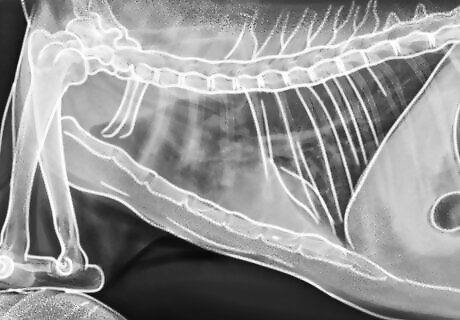

Notice labored breathing. Pneumonia is also a symptom of toxoplasmosis, although it is less common. If you notice a shortness of breath, wheezing, coughing, and/or shallow, rapid breathing, then your cat may have pneumonia as a result of toxoplasmosis. Take your cat to the vet immediately if you see your cat struggling to breathe with its mouth open.